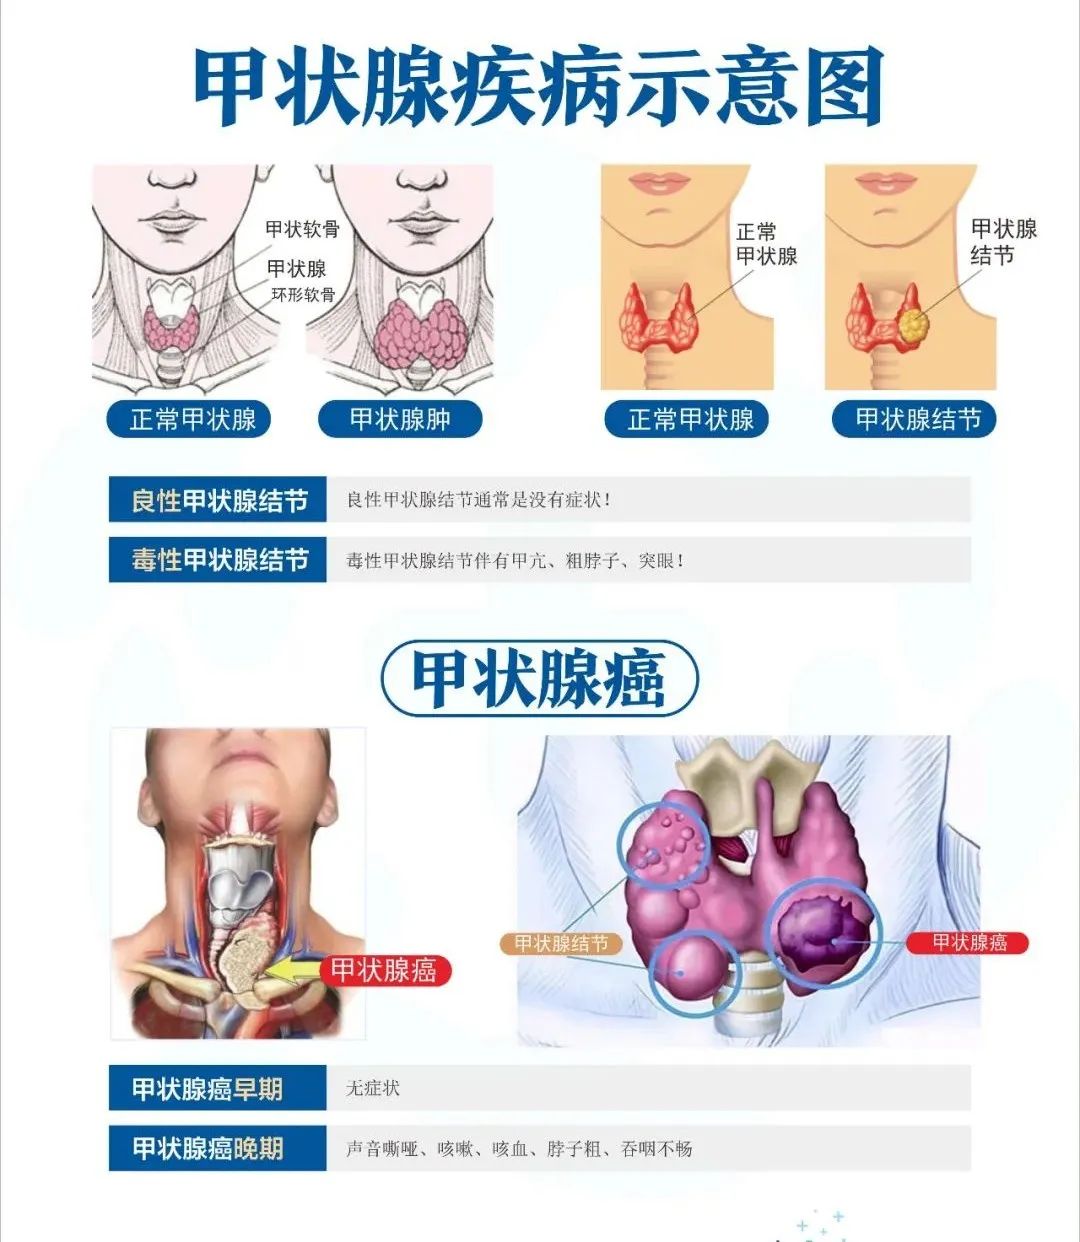

天天有专家丨陕西冶金医院开设综合外科专家门诊,甲乳外科正式开科!

2/0/2/2 陕西冶金医院 开设综合外科专家门诊 甲乳外科开科 大医精诚为信念为病人服务为中心 0 1 综合外科专家门诊 周末专家门诊 为进一步方便患者就医,满足患者不同时段的就诊需求